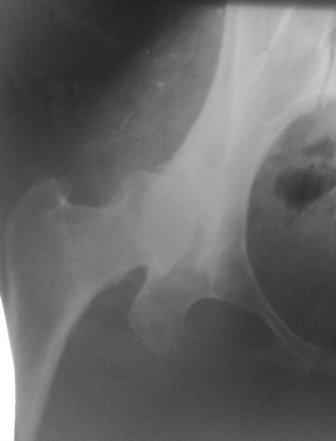

Представляю Р-снимки: обзорная, с отведением и с приведением.